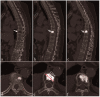

This case report describes a rare giant bone island combined with hemangioma diagnosed in a patient with osteolytic vertebral metastases. The bone island's greatest diameter was 3.15 cm, and bone islands of this size are rare in the literature. This article aims to provide clinicians with information about the diagnosis and relevant literature of bone islands.